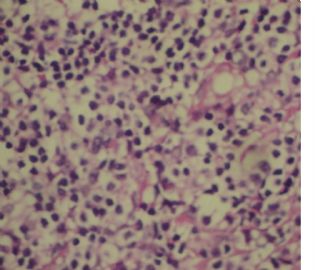

标本名称:  左前臂数个大小不等的皮下肿物。

既往有非何杰金淋巴瘤(滤泡性淋巴瘤)病史22个月。

• 左前臂数个大小不等的皮下肿物     淋巴瘤?图3

图3

病例不错。细胞胞浆透亮,间质血管丰富,图片不是很清晰,似乎有嗜酸粒细胞?

恶性,首先考虑T-NHL。IHC证实。

既往有NHL病史,图片不太清晰,细胞弥漫,胞浆透亮,首先考虑T细胞淋巴瘤。